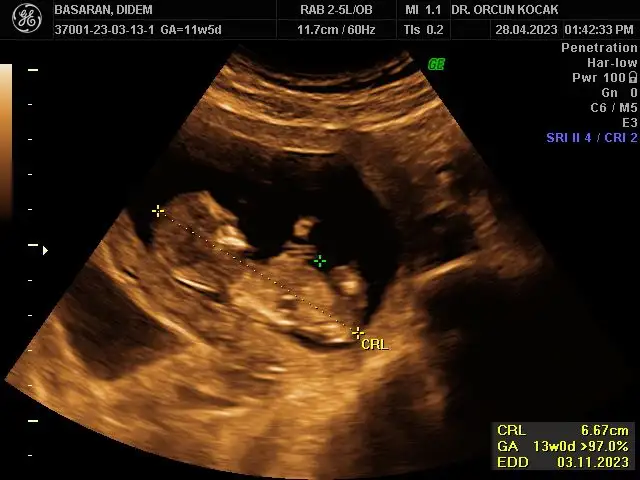

Merhabalar bende 11+5 im tahminlerinizi çok merak ediyorum kızlar sizce ne olabilirRamzi de nub’ u da erkek görünüyor canım

Bu ultrason görüntüsü mü yoksa alttan mı? Ultrasonsa benimkiyle aynı da kafatası bile. Ay ultrason yazmışsın zaten ya farketmedim. Sağlıkla kucağına al inşallah evinize neşe getirsin.Ultrason görüntüsü bugünün böyleydiben erkek hissediyordum bu sefer bulantım filan olunca ama değilmiş hiç teorilere bakmadım açıkçası o yüzden bilmiyorum